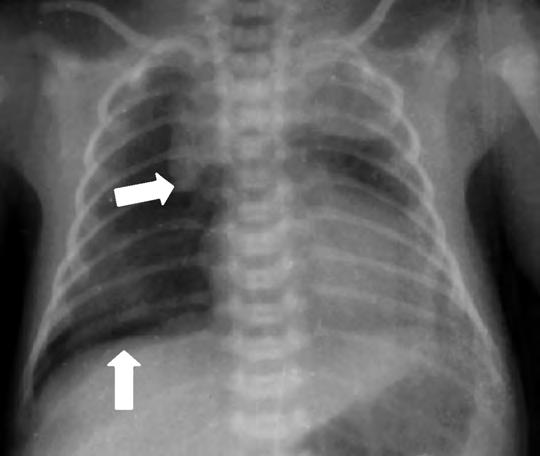

El patrón radiológico es muy variable y no guarda buena correlación con la gravedad clínica. Inicialmente se caracteriza por zonas infiltrativas con imágenes hiliofugales de intenso refuerzo junto con áreas de hiperinsuflación, y aire extraalveolar (Fig. 2.17.2). En las formas más graves suele predominar la imagen de atelectasia, edema y bajo volumen pulmonar probablemente por la inactivación del surfactante y fallo cardiaco relacionado con el episodio asfíctico concomitante.